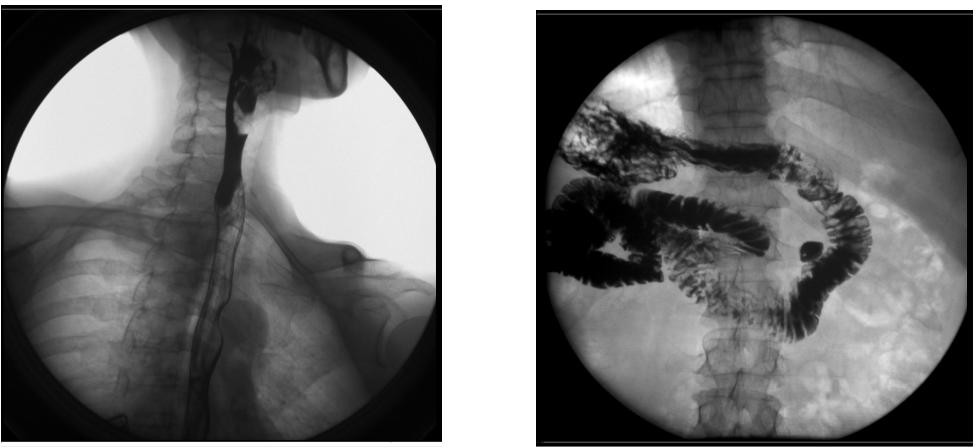

【臨床圖像】